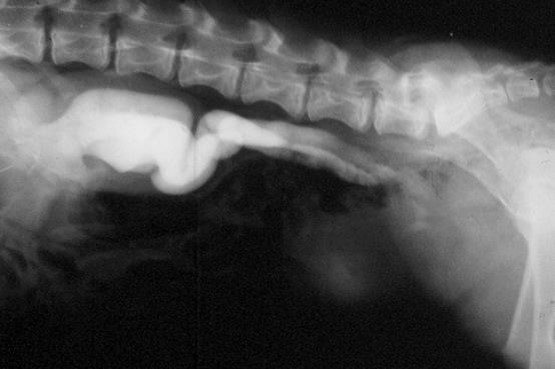

What does this show?

Left – large soft tissue structure. Non contrast; non filtering enlarged L kidney

R – some contrast in ureter and leaving renal pelvis